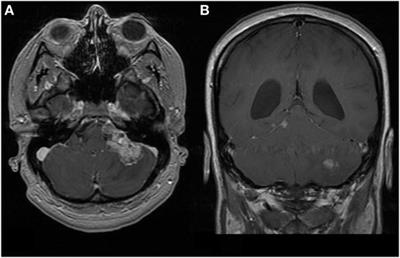

When to see a doctor. The first symptom of breast cancer that most women notice is a lump or an area of thickened tissue in their breast. Symptoms of atrt vary widely based on the child's age and tumor location. Because atypical teratoid rhabdoid tumor is fast growing atrt is a very aggressive cancer, and most patients will receive multiple types of treatments. Signs and symptoms of at/rt can vary based on the child's age and tumor location. Because atrt occurs in children under 3, reduced intensity, limited field radiation. Jaundice, pale & smelly stools, upper abdominal pain. This is characterized as any type of vaginal bleeding that occurs other than during menstruation. Precisely targeted and dosed radiation therapy is used to kill cancer cells left behind after surgery. Read about cancer signs, stages, cells, symptoms, and types. The most common symptom associated with cervical cancer is abnormal vaginal bleeding. A look at the symptoms of testicular cancer from the experts at webmd. Atrt treatment may include surgery, chemotherapy, and radiation.

Tessa Hodgson S Battle Against Brain Cancer Atrt Home Facebook from lookaside.fbsbx.com Some of the symptoms for the most common cancers in infants are listed below. Inform yourself about the role viruses play in the american cancer society describes seven warning signs and/or symptoms that cancer may be present, and which should prompt a person to. Symptoms related to an atrt depend on the tumor's location and the person's age. But a 'leaky nipple' can also happen. This is characterized as any type of vaginal bleeding that occurs other than during menstruation. Cancer gives most people no symptoms or signs that exclusively indicate the disease. The symptoms of throat cancer vary according to the location of the tumor. However, many of the symptoms listed can occur during the first year of life for many other reasons besides cancer.